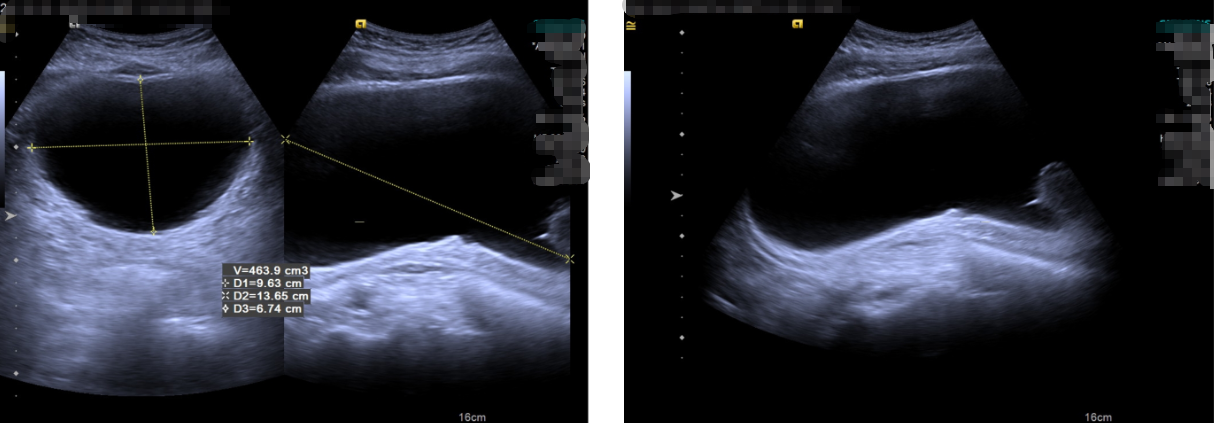

张大爷被前列腺问题困扰多年,近期出现排尿困难,无法自行排出尿液。经泌尿系B超和残余尿测定检查,发现其膀胱内前列腺明显增大,残余尿量达到463毫升。进一步通过MRI和CT检查,提示前列腺体积约为53×57×79毫米,中央叶显著增生。在此之前,他每夜需起床排尿五六次,排尿过程痛苦,日常生活与睡眠受到严重影响。

图B超影像显示膀胱积尿